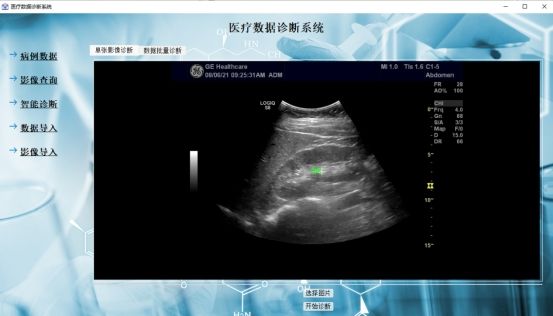

主程序界面如下,

img

主界面分為病例數(shù)據(jù)、影像查詢、智能診斷、數(shù)據(jù)導(dǎo)入、影像導(dǎo)入五個(gè)分界面,各個(gè)界面將實(shí)現(xiàn)不同的功能,詳細(xì)功能在以下內(nèi)容中將詳細(xì)展示。